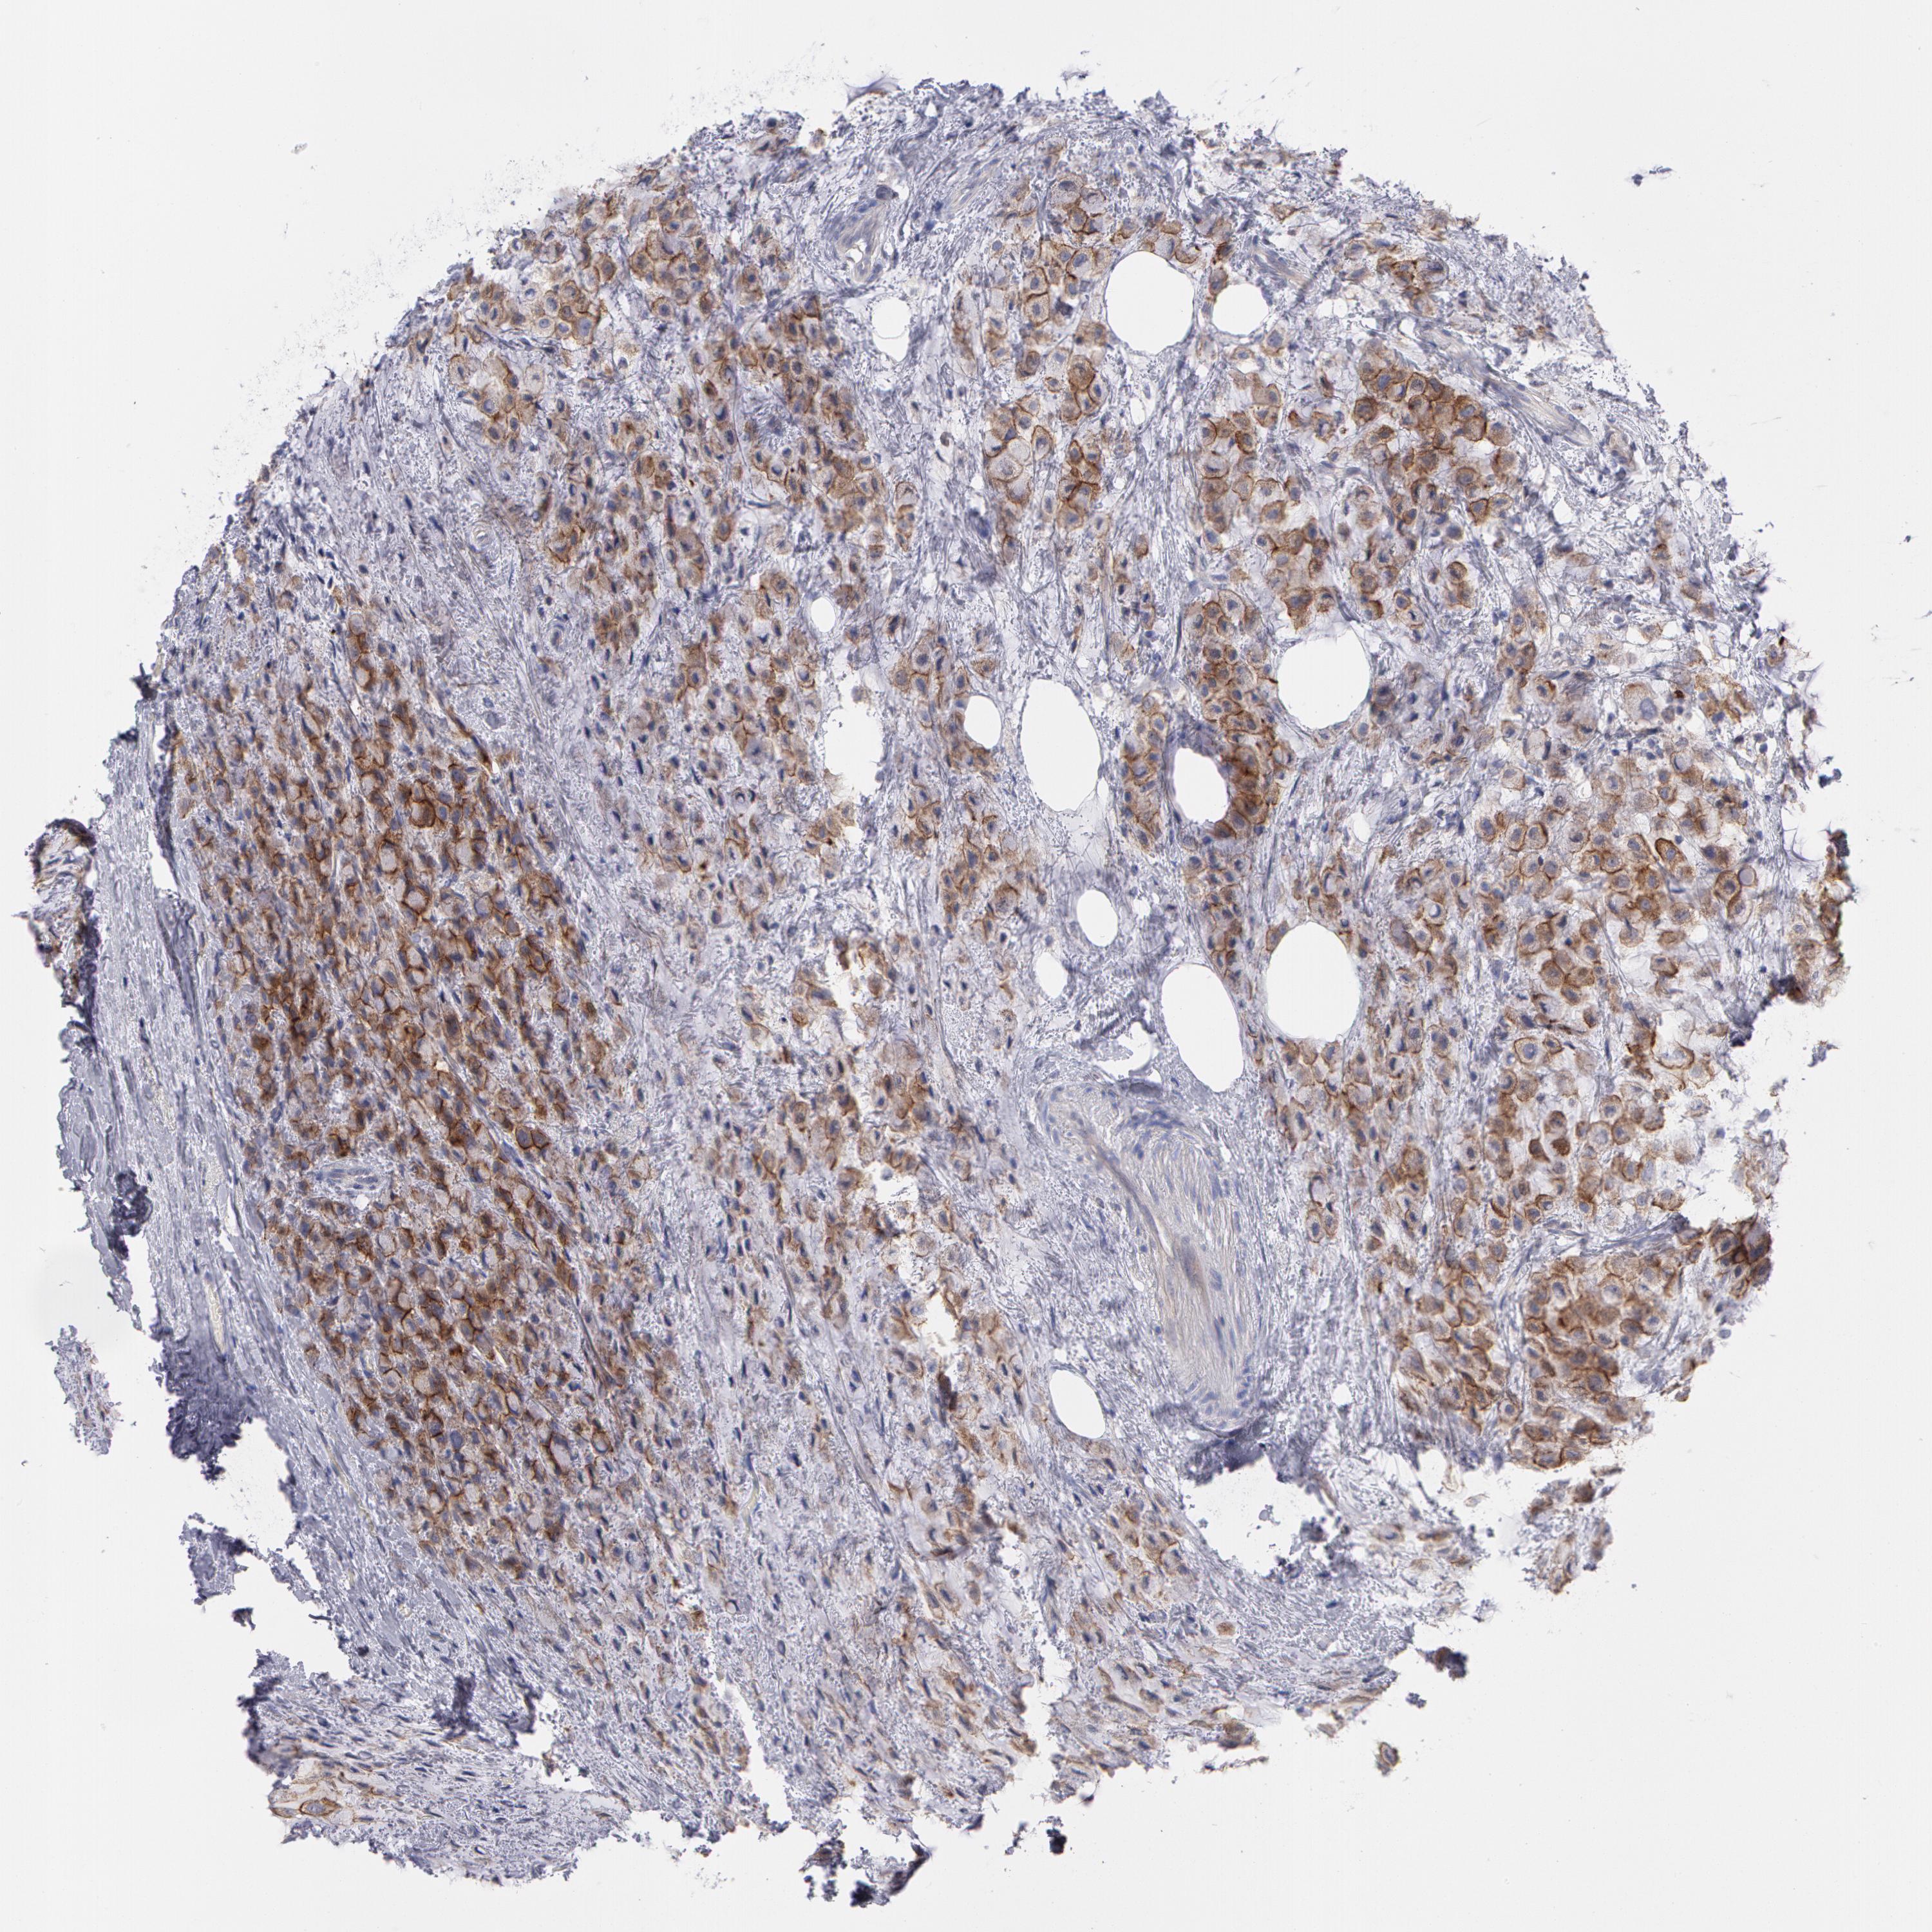

• ERBB2

CANCER BREAST CANCER Show tissue menu

Breast cancer

Human cancer